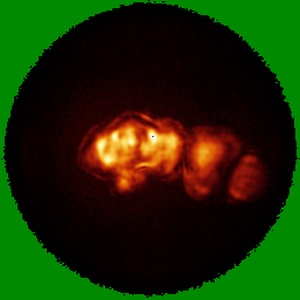

RBD in complex with Fab14

Single-particle7.3 Å

Sample: RBD bound to Fab14